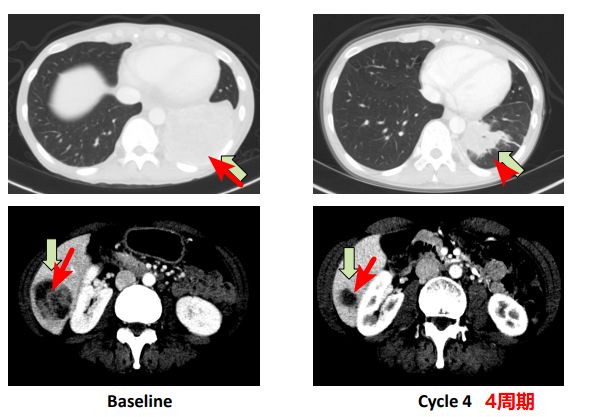

肺癌患者:治疗4个周期后,肿瘤明显减小。